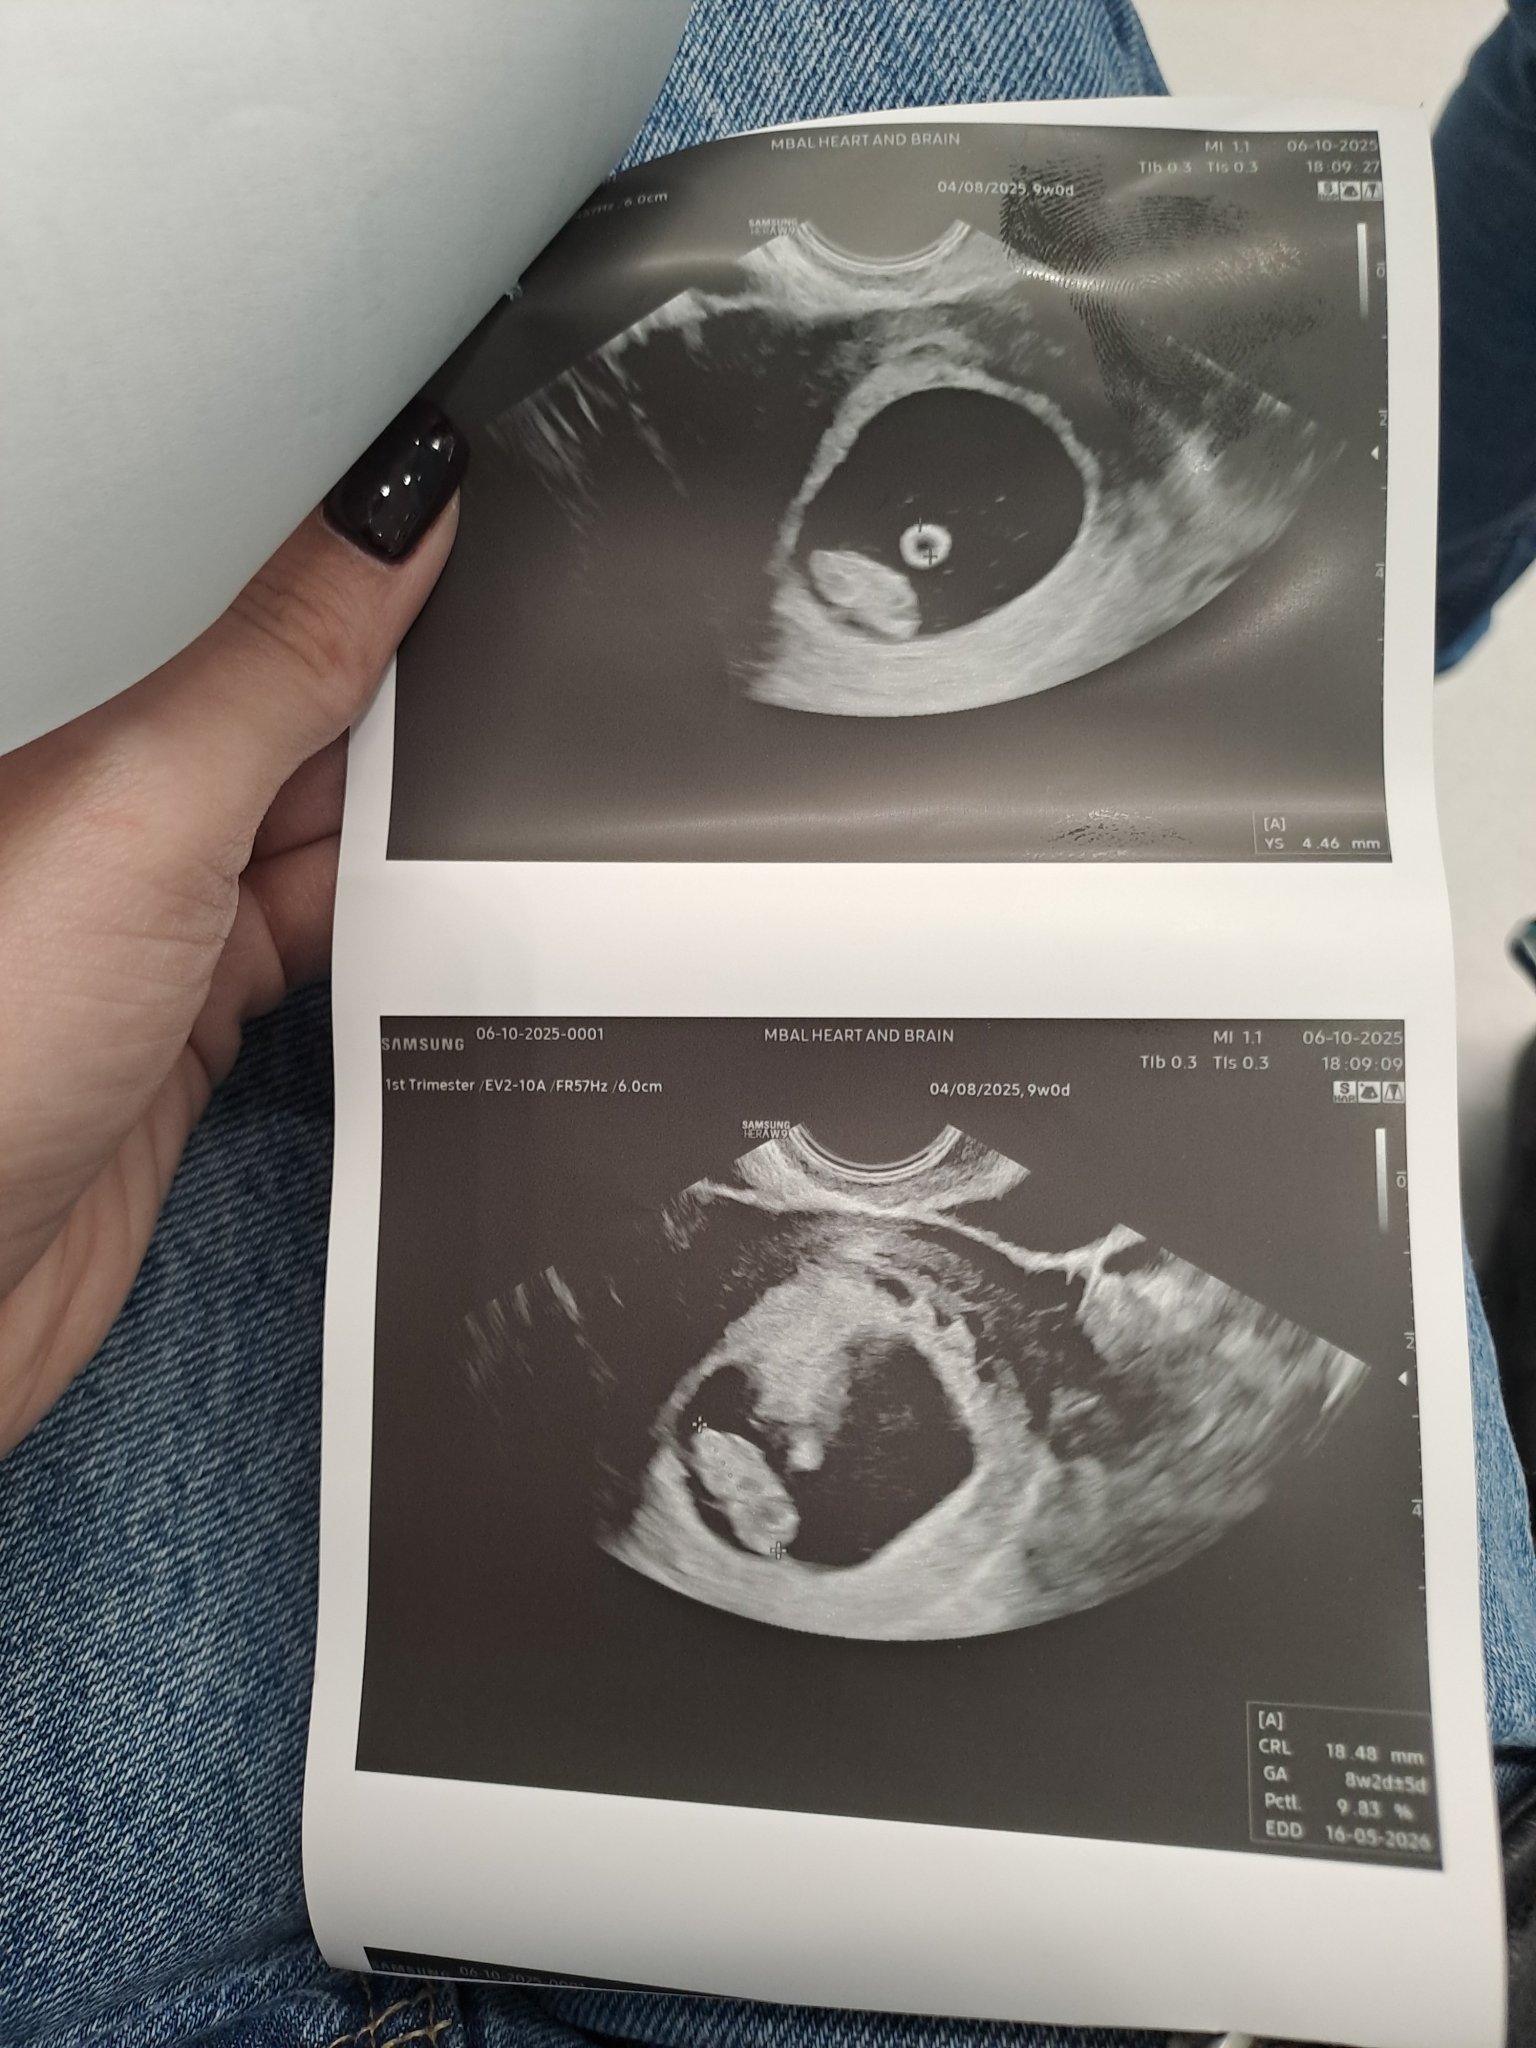

Кога обикновено може да се види ембрионът на ултразвукова снимка?